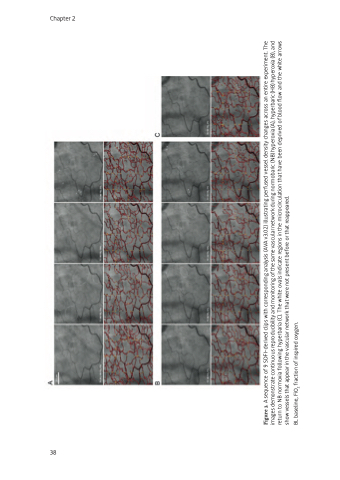

Figure 3. A sequence of 9 SDFI-derived clips with corresponding analysis (AVA v3.02) illustrating perfused vessel density changes across an entire experiment. The images demonstrate continuous reproducibility and monitoring of the same vascular network during normobaric (NB) hyperoxia (A), hyperbaric (HB) hyperoxia (B), and return to NB normoxia following hyperbaria (C). The white ovals indicate regions in the microcirculation that have been deprived of blood flow and the white arrows show vessels that appear in the vascular network that were not present before or that reappeared.

BL baseline, FiO2 fraction of inspired oxygen.